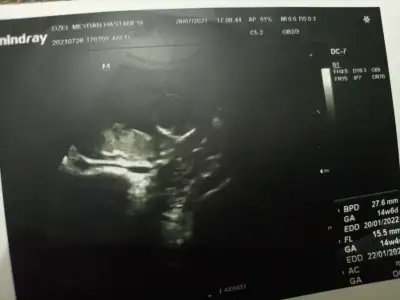

Erkek gibi ama başka usg olursa paylaşınsevgiliIkra meyra bizimkine de bakar mısın? ne göreceksin çok merak ediyorum, teşekkürler :) 11 hafta ultrasonu.

aynı günden bunlar da var ama daha net olanları seçmeye çalışmıştım :)Erkek gibi ama başka usg olursa paylaşın![]()

12-13 hafta olursa paylasin net değilaynı günden bunlar da var ama daha net olanları seçmeye çalışmıştım :)